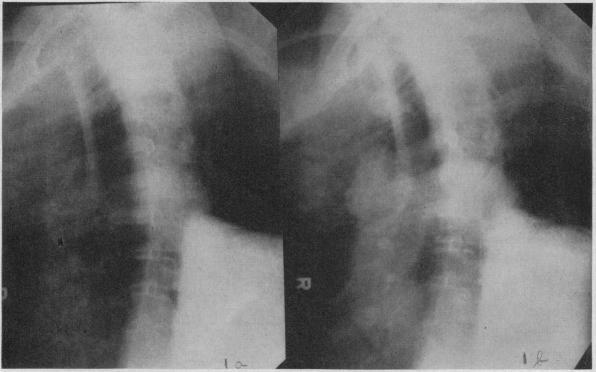

Angiocardiography is indicated in selected cases of heart disease in which a definite diagnosis cannot be made by ordinary methods or in which there is reasonable expectation that the information so obtained may influence the treatment of the patient. Whenever possible, angiocardiography should be done in conjunction with cardiac catheterization. The main indication for angiocardiography is cyanotic congenital heart disease; primarily those cases in which there is a right-to-left shunt. Angiocardiography is occasionally of value in diagnosis of other types of congenital heart disease and in acquired heart disease.